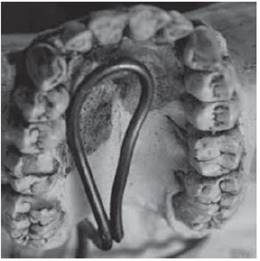

In some instances fourth molars fuse to third molars, and appear as a tubercle appended to its crown in the distal-lingual area, it is then called distomolar tubercle, it can even be appended to the third molar roots such as the palatine root in the case described by Gay-Escoda, Berini, Duarte and Azevedo14,15(Figure 6).

It has been reported that a lingual extension of the dental lamina will result in a eumorphic tooth (Figure 10), and epithelial remnants induced by dentition pressure will result in a dismorphic tooth (Figure 11).12,16,18